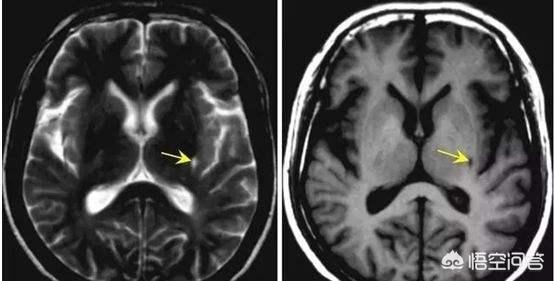

Vingt-quatre à 48 heures après l'apparition de l'infarctus cérébral, la tomodensitométrie du cerveau montre des foyers de faible densité dans les zones correspondantes, avec des limites mal définies, qui peuvent avoir un certain effet d'occupation. L'examen par résonance magnétique cérébrale (IRM) permet de détecter l'infarctus cérébral à un stade plus précoce, ce qui se manifeste par un signal T1 faible dans la zone de la lésion et un signal T2 élevé sur l'image pondérée, et l'IRM permet de détecter des foyers d'infarctus plus petits.

Les lésions d'infarctus cérébral caverneux sont petites et ne sont facilement reconnaissables que par les spécialistes, avec des lésions multiples au milieu de la section cérébrale de l'IRM.